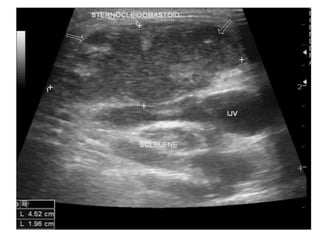

Ultrasound

• Ultrasound is an excellent first-line investigation as it

assess cervical lymphadenopathy and also enables

guided fine needle aspiration cytology.

• The combination of grey-scale imaging and FNAC as a

sensitivity of 92% and specificity 97% in distinguishing

benign from malignant nodal disease.

• Differentiating features from neck metastasis include:

– Nodal matting

– Surrounding soft tissue oedema (less marked than one

would expect given the size of the collections)

– Homogeneity

– Intranodal cystic necrosis and

– Posterior enhancement.

• Doppler examination is particularly useful in

helping distinguish tuberculous infection from

necrotic metastatic disease.

• Reactive nodes (including those in tuberculous

lymphadenitis) demonstrate prominent

vascularity, but mostly confined to the hilum,

whereas malignant nodes demonstrate more

peripheral/capsular vascularity.